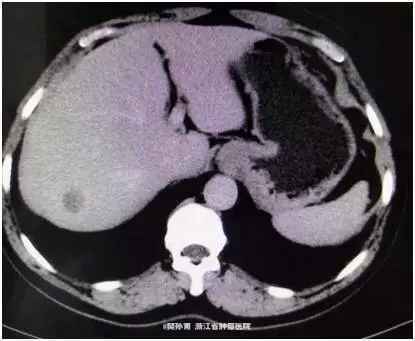

查体:心肺查体阴性,腹平软,无腹壁静脉曲张,全腹无压痛、反跳痛,腹部无包块。肝脏未触及,脾脏未触及,Murphy氏征阴性,肝、肾、脾无叩击痛,无移动性浊音。肠鸣音正常。 肿瘤标志物阴性。 CT表现:动脉期:肝包膜光整,肝脏形态正常,肝右叶可见低密度结节。大小约1.8*2.4 cm。边界模糊。门脉期:病灶强化幅度减低,边界较动脉期清晰。延迟期:病灶仍呈低密度。肝内胆管不扩张,肝门结构清晰自然,胆囊不大,壁光滑,腔内未见明显异常。脾脏、胰腺、胃、腹膜后未见明显异常。

初步诊断:肝脏占位,性质待查。 术中探查见于右肝后叶扪及一大约3x2.5 cm肿块,质硬,余肝未扪及异常,腹腔无肿大淋巴结,腹腔其它脏器未见异常。

如何诊断?以下几个选项,大家来讨论下? 1、局灶性结节增生 2、肝血管瘤 3、原发性肝癌 4、肝腺瘤 5、肝坏死结节 6、肝囊肿